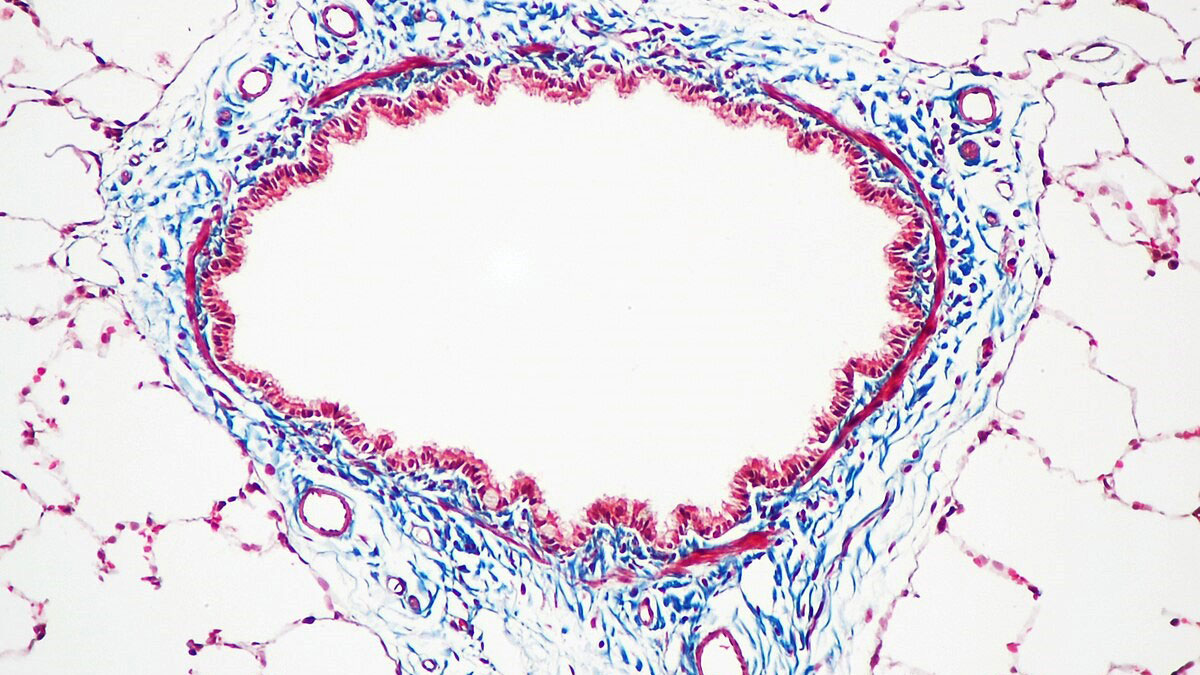

در مقابل، رنگآمیزیManson Trichrome و سایر تریکرومها مانند Mallory و Gomori بیشتر در بافتشناسی (Histology) کاربرد دارند و برای بررسی بافتهای همبند، کلاژن، عضله و تغییرات فیبروز به کار میروند. این روشها معمولاً روی مقاطع بافتی فیکساتشده و پارافینگذاریشده انجام میشوند و هدفشان شناسایی ساختارهای بافتی و فیبریلها است، نه مشاهده پروتوزوآهای رودهای. تفاوت اصلی این روشها با Wheatley Trichrome در نوع نمونه، ترکیب رنگ، ساختار هدف و فیکساتور مورد استفاده است.